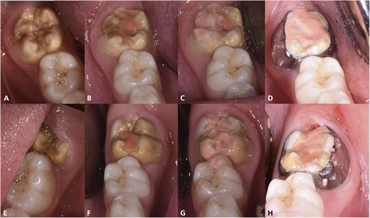

The diagnosis of MIH depends on the affected teeth and the pattern in which they are hypomineralized. Spot lesions more than 1 mm in diameter and of whitish, yellowish or brownish opacities are commonly seen. The incisors and the molars are commonly affected. In more severe cases, the hypomineralization can spread to other teeth.

Patient can present with teeth that are gradually breaking or whose layers are gradually chipping off. They also have a high dentinal sensitivity and are prone to multiple cavitations.

Treating MIH teeth is one of the most challenging tasks in dentistry. The patients have a very high pain sensitivity and anesthesia's effect is very less in these patients. The goal of MIH treatment is to remineralize the tooth and also retain the esthetics. Remineralization can be achieved by prescribing toothpastes containing Casein Phosphopeptide Amorphous Calcium Phosphate (CPP-ACP), Fluorides, Hydroxyapatite or Novamin.

Removal of carious lesions is done along with local anesthesia infiltration. Of all anesthetic agents in dentistry, 4% articaine is the most effective for MIH teeth. Once the carious lesions are removed, the tooth can be restored with full coverage crowns or adhesive cements. Challenges can be faced when the dental cements do not adhere to the tooth structure due to poor mineralization.